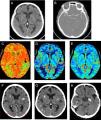

Angiopatía amiloide como causa de “hemorragia intracraneal remota” en paciente tratado mediante fibrinólisis

Amyloid angiopathy as a cause of “intracranial remote hemorrhage” in a patient treated with fibrinolysis